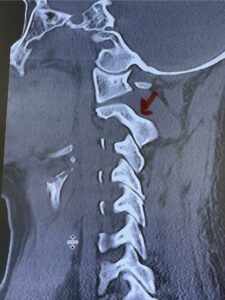

Fig. 6c: Axial cervical CT scan demonstrating a very thin right C2 isthmus (red arrow) compared to left side.